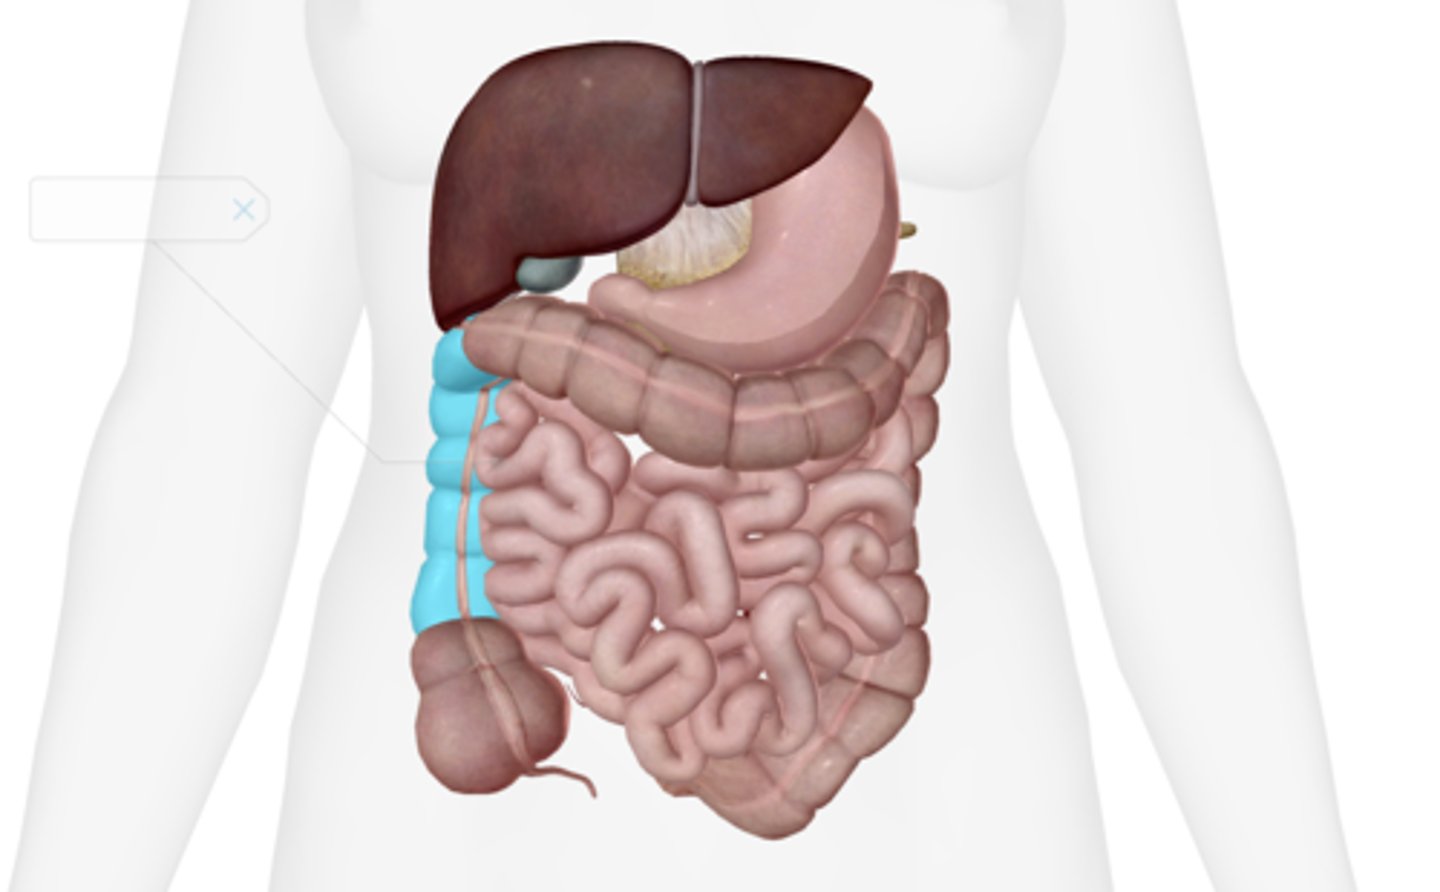

Ascending colon